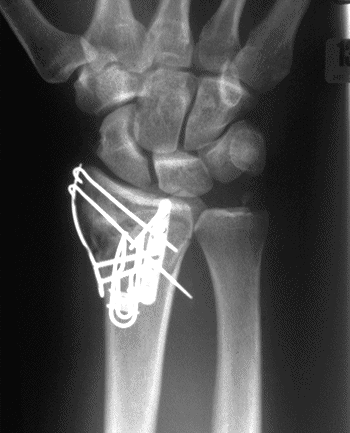

Case 1 Postop